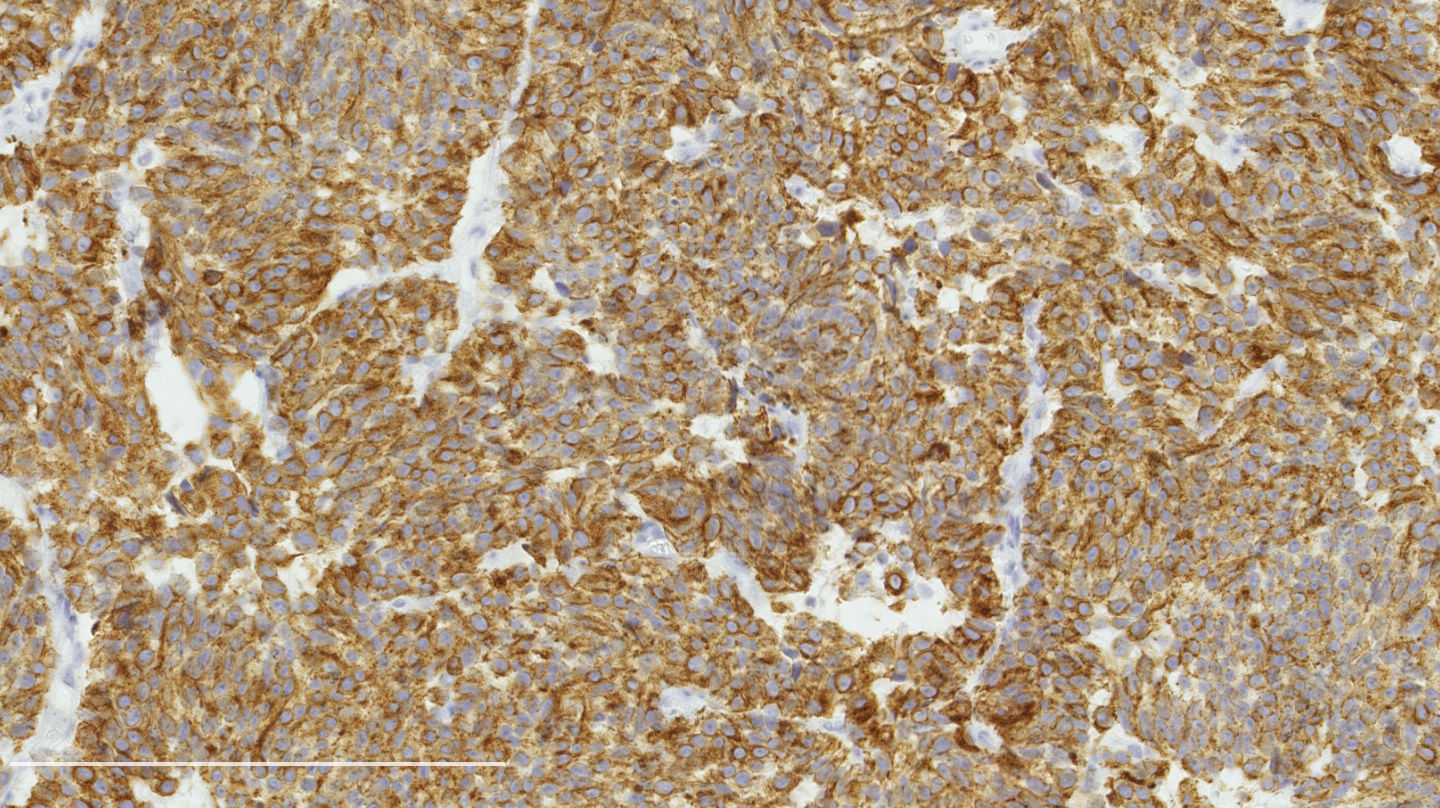

Contributed by Philippe Joubert, M.D., Ph.D.

Positive stains

- Chromogranin, synaptophysin, CD56: diffusely and strongly positive; can be negative in a small number of atypical carcinoids (Hum Pathol 2000;31:1255)